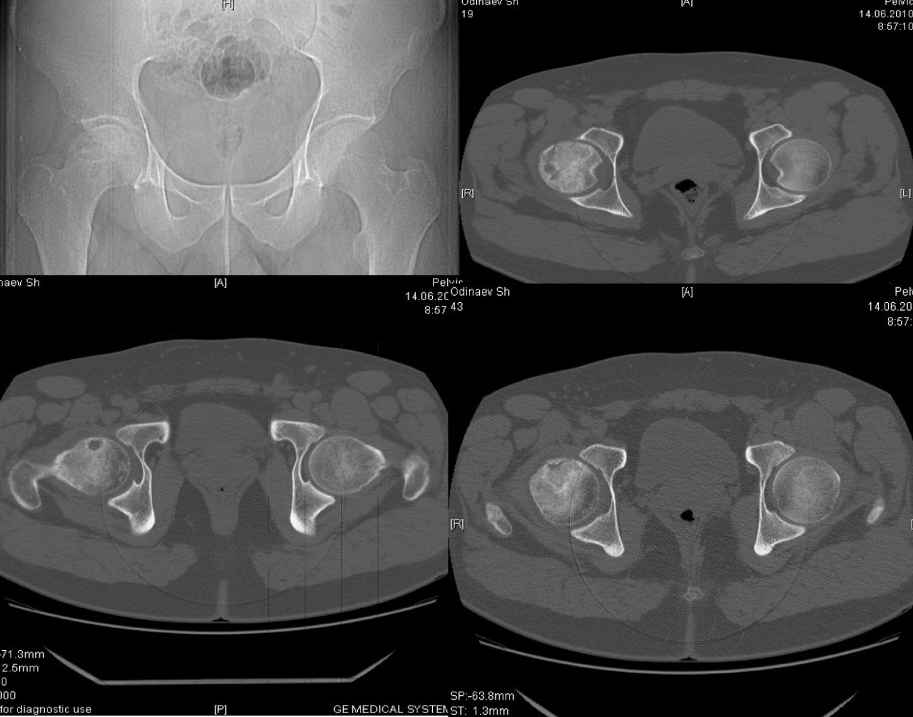

[Ortho] асептический некроз головки бедренной кости

доброго времени суток уважаемые коллеги.Обратился пациент,30 лет жалуется на боли в

области правого т/бедренного сустава, хромоту.

При внутренней ротации болезнгенность.Болеет в течении 3 мес. Снимки во вложении. Больной

получает курс консервативной терапии. Из хондропротекторов ДОНА порошок. Хотелось бы

услышать мнение уважаемого сообшесва по поводу консервативной терапии, может у кого из Вас

имеется опыт по консервативной терапии с применением более эфективной медикаментозной

терапии. что касается эндопротезирования мы считаем, что в таком возрасте показания

относительные. Спасибо.